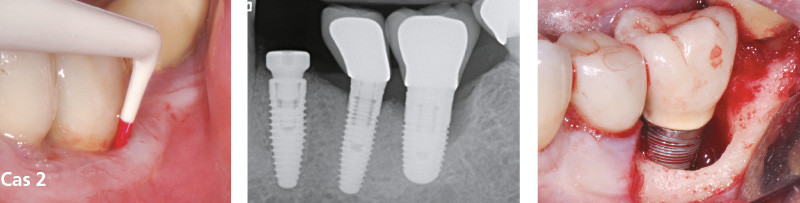

Les péri-implantites avancées : traiter ou déposer ?

Les péri-implantites sont pour la plupart asymptomatiques et le diagnostic est souvent tardif. Le praticien est donc confronté à des pertes osseuses péri-implantaires souvent sévères pouvant représenter plus de la moitié de la hauteur de l’implant. De plus, la morphologie des lésions osseuses associées peut être plus ou moins complexe.

La régénération autour des implants, décrite dans la littérature et faisant l’objet de nombreuses conférences parfois spectaculaires, n’est pas toujours prédictible et dépend de multiples facteurs [6-8].

Il est donc logique de se poser la question, face à une péri-implantite sévère, de la conservation ou de la dépose de l’implant atteint. Il n’existe aujourd’hui dans la littérature aucun arbre décisionnel concret pour cette prise de décision : traiter ou déposer ?